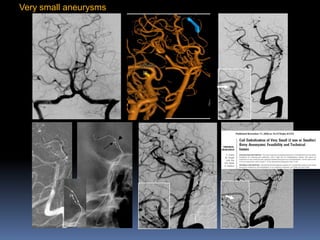

Very small aneurysms

? Near the neck rupture/lobule

Catheter reposition

1-mm coil

Branch from aneurysm-Overinflationtechnique